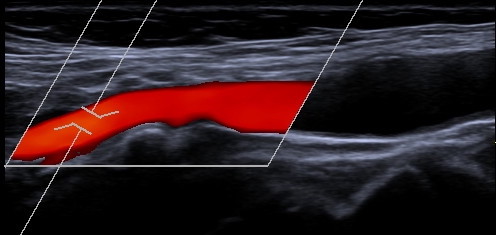

Gefäßdarstellung mittels Ultraschall

Bei der Doppler-Duplex-Sonographie der Halsgefäße wird untersucht, ob Verkalkungen (Plaques) vorliegen, und ob es dadurch zu Verengungen (Stenosen) kommt.

Neben dem Aussehen der Plaques wird die lokale Flussgeschwindigkeit des Blutes beurteilt: Je schneller die Flussgeschwindigkeit, desto hochgradiger die Stenose.